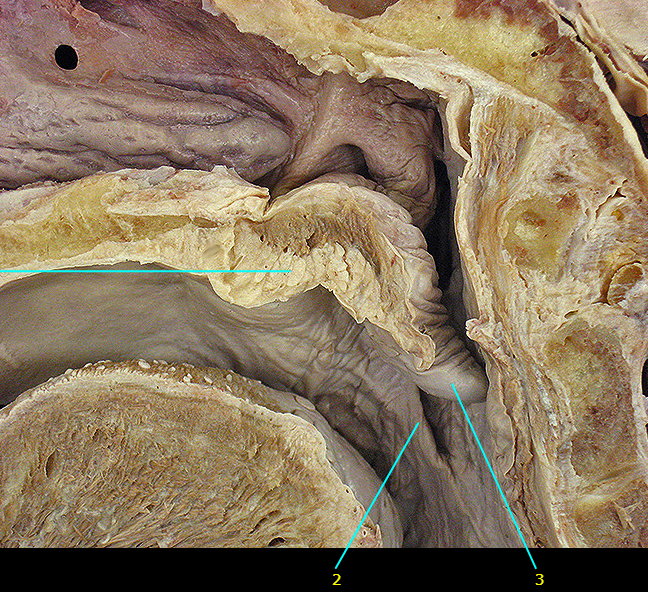

Name #3

Epiglottis (epiglottic cartilage)

Levator veli palatini m.

Torus levatorius